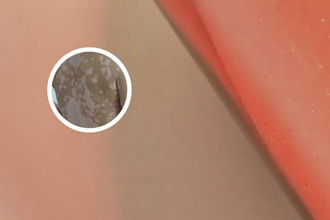

白點癲在皮膚鏡下呈現(xiàn)為白色斑點狀或小片狀的色素缺失區(qū)域。這些缺失區(qū)域一般較小且零散分布,形狀不規(guī)則,經(jīng)常無規(guī)律地散在皮膚各處。白點癲周圍的正常皮膚可能出現(xiàn)輕度紅斑或色素沉著,形成對比。

皮膚鏡下觀察還可以看到白點癲病變區(qū)域的毛細(xì)血管改變,通常表現(xiàn)為毛細(xì)血管網(wǎng)的擴(kuò)張和充血。這種改變反映了白點癲病變區(qū)域血流的異常,可能與色素沉積和色素缺失有關(guān)。

在皮膚鏡下觀察,白點癲的斑塊通常會出現(xiàn)表皮層的變化。由于色素細(xì)胞的損害,斑塊區(qū)域的表皮層會呈現(xiàn)出顯然的色素減少或消失現(xiàn)象。同時,表皮層也可能出現(xiàn)角化不良或過度角化的現(xiàn)象,使得斑塊區(qū)域與周圍皮膚表面有所不同。

色素細(xì)胞是控制皮膚顏色的主要細(xì)胞,對白點癲的觀察中十分重要。在皮膚鏡下,可以看到斑塊區(qū)域的色素細(xì)胞數(shù)量減少或盡量喪失。一些文獻(xiàn)還提到,在白點癲的斑塊中,部分色素細(xì)胞可能會發(fā)生退化,變得異常扁平或不規(guī)則形狀。

3. 微血管的變化